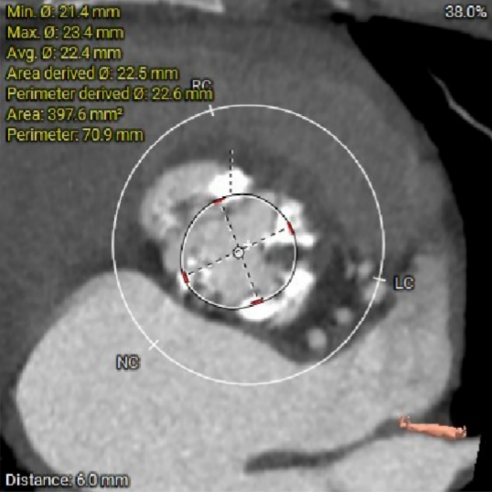

主动脉根部CTA:

根部概览:

虚拟瓣环与水平夹角

图片

术前考虑右侧股动脉为主入路,左侧为辅助入路。非横位心,主动脉弓角度、宽度尚可,预估输送器过弓难度适宜,跨瓣难度适宜,术中必要时采用Snare辅助。左右冠脉开口高度可,左冠切线角度测量瓣叶大于LCA开口下缘到根部距离,结合瓦氏窦及STJ尺寸预估,冠脉风险适中,建议术中密切关注左冠灌注情况。外周入路走行适宜,腹主中下端和左右髂总散在钙化,血管内径尚可,血管内壁存在不规则纤维增厚和钙化斑,入路穿刺规范操作,小心通过,避免入路血管损伤及相关并发症。重度钙化二叶式病变重度主动脉瓣狭窄,其瓣口面积小,瓣口限制明显,术中瓣膜锚定难度较大,瓣膜植入受二叶瓣瓣叶及团块状钙化挤压存在移位及少量偏多瓣周漏风险,为避免手术并发症,手术预装AV26瓣膜,根据20mm球囊预扩结果选择瓣膜型号,计划瓣膜瓣上3mm开始释放。